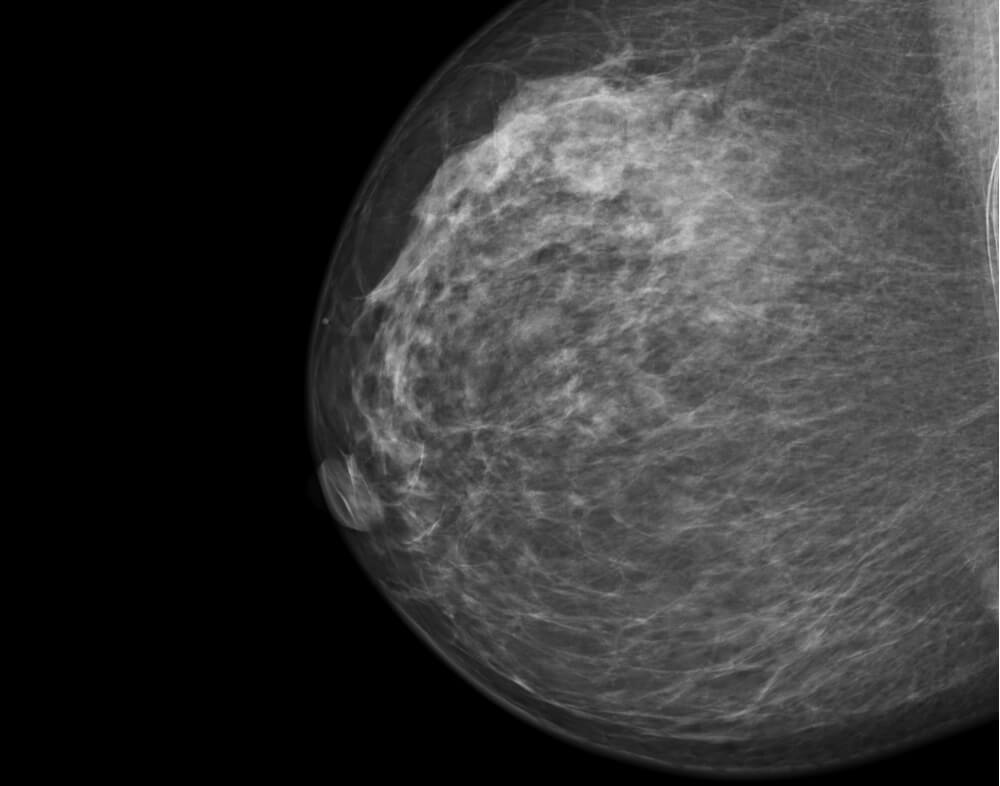

Κατά τον έλεγχο με μαστογραφία και υπερηχογράφημα συχνά συγχέονται με κακοήθεια.

Ο έλεγχος με μαγνητική τομογραφία είναι ενδεικτικός καλοήθους βλάβης.